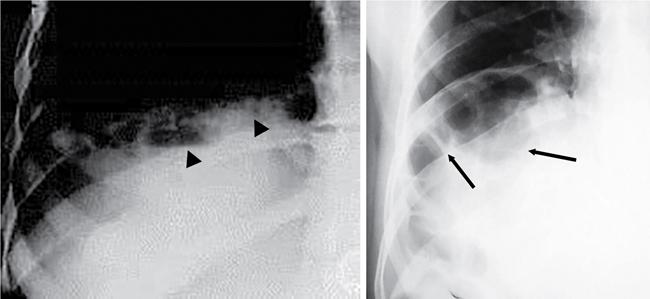

UNDERSTANDING THE ADULT ABDOMINAL RADIOGRAPH: TECHNIQUES AND INTERPRETATION Tanvi Modi Radiography of the abdomen is a common practice for the evaluation of abdominal organs. The anatomy and pathology of digestive, hepatobiliary and genitourinary systems can be assessed using radiographs, either as a stand-alone practice or as a primary imaging modality followed by contrast studies, ultrasound or cross-sectional imaging. In addition, abnormalities of the musculoskeletal or integumentary system can also be deduced on the basis of abdominal radiographs. This chapter intends to give an overview on the techniques and positioning in abdominal radiography as well as interpretation of normal and abnormal features. While superior imaging modalities such as ultrasound, computed tomography (CT), magnetic resonance imaging, capsule endoscopy and the likes have taken over abdominal imaging by and large, radiography still holds a pivotal role in certain situations and conditions, such as: The standard abdominal radiograph is taken in supine position and anteroposterior projection. This is also popularly known as the KUB (kidneys-ureters-bladder) radiograph. Previously, supine as well as erect radiographs were performed in all patients; however, this is not commonly done due to high-radiation dose. For all indications of abdominal radiography, including acute abdomen, supine radiographs are sufficient in terms of radiographic diagnosis, with the exception of perforation for which an erect chest or lateral decubitus radiograph can be performed if there is clinical suspicion. Patient should lie supine on the imaging table with median sagittal plane at right angles to the table and coincident with the midline of the table (Fig. 7.1.1.1). The body is divided into equal right and left halves by the median sagittal which passes through the sagittal suture of the skull. Pelvis should be adjusted so that the anterior superior iliac spines are equidistant from the table top. Gonadal shields, in the case of male patients, should be placed with the upper edge of the shield at the level of pubic symphysis. Although rarely used for female patients, these should be positioned between the anterior superior iliac spines and the pubic symphysis. The centre point of the image receptor should be approximately located at a point 1 cm below the line joining the iliac crests. The X-ray beam should be in a vertical direction, perpendicular to the table top and image receptor at the centre point. Collimation should be such that the soft tissue and subcutaneous region along lateral aspects of the abdominal cavity should be covered within the image. Also, the superior extent involving diaphragm and inferior extent involving the inferior pubic rami is important to look for any lower chest pathologies or any inguinal hernia. 35 × 43 cm (14 × 17 inches) in portrait orientation. On an average, abdominal radiograph exposes a patient to a dose of approximately 1.5 mSv, which is equivalent to 75 chest radiographs or 1/6th dose of a standard CT of the abdomen. The entrance skin dose is approximated to be 4 mGy. At such an effective dose, the additional lifetime risk of fatal cancer is 1 in 30,000. The exposure time is kept short. Patient is asked to exhale completely and hold their breath, with exposure taken at this point of full expiration to ensure imaging of abdominal organs in their natural positions. Modifications of this technique can be made depending on patient habitus and clinical condition. Kilovoltage peak (kVp) should be set to allow adequate visualization of abdominal soft tissue structures as well as semiopaque renal and biliary calculi. Average kVp is set at 70–85 kV. 102 cm (40 inches) Grids are commonly used to reduce scatter radiation. Placement of side marker on the image receptor at the time of radiographic exposure is essential. Bowel pattern depiction should be such that there is minimal lack of sharpness. Standard guidelines for abdominal radiography dictate that the radiograph should extend from the diaphragm up to the level of inferior pubic rami and must include the lateral abdominal wall musculature. The abdomen is divided into four quadrants on the basis of two perpendicular lines (Fig. 7.1.1.7). The vertical line passes through the mid sagittal plane and crosses the umbilicus and symphysis pubis. The horizontal line is a transverse line across the umbilicus at 90 degrees to the vertical line and is situated at the level of L4–L5 intervertebral disc. The quadrants are as follows: Another division system is dividing the abdominopelvic cavity into nine regions using two vertical and two horizontal planes (Fig. 7.1.1.8). The vertical planes, also known as the right and left lateral planes, are parallel to the midsagittal plane between midline and anterosuperior iliac spines on either side. Of the two horizontal planes, the upper transpyloric plane is at the level of lower border of L1 and the lower transtubercular plane is at the level of L5. The nine regions are: On a standard radiograph, the exposure should be such that the stomach, bowel loops, outlines of liver, spleen, kidneys, psoas muscles should be well identified. Also, lumbar transverse processes should be seen. Arch of the pubic symphysis should be visible to evaluate bladder region. A well-centred film without rotation will demonstrate bilaterally symmetrical lower ribs, iliac wings, ischial spines and obturator foramina. Different structures seen on an abdominal radiograph can be classified into five basic densities: Identification of different structures depends on the relative degree of contrast between their densities. The demarcation is clearer in chest and is diminished in abdomen due to relative similar soft tissue density of various structures. On a normal radiograph, relatively large amounts of gas in stomach and colon with minimal small bowel gas can be seen. Further, colonic gas can vary from negligible to extensive, mimicking obstruction pattern; however, usually the gas is enough to delineate colonic haustral pattern. Faecal matter gives a mottled appearance to colonic gas. Short-air fluid levels on an erect radiograph may be seen even in normal cases. The normal appearance of small bowel loops on an abdominal radiograph follows the rule of threes: Stomach is seen in the left upper quadrant and is visualized when distended with air. It is commonly seen extending from T11 to L2 level. Common feature identifying the stomach is the fundal gas which is usually seen as an air fluid level within the gastric lumen. Small bowel loops are distributed to the centre of the abdominal cavity and large bowel loops are peripheral. Duodenum is predominantly situated in right upper quadrant. It extends to left upper quadrant in the region of duodenojejunal flexure. Jejunum occupies the left upper and lower quadrants and is easily identified due to the presence of thick, numerous, closely spaced valvulae conniventes (Fig. 7.1.1.9A). The ileum occupies both lower quadrants and extends into right upper quadrant. Ileum has few and less prominent valvulae as compared to jejunum (Fig. 7.1.1.9B). Ascending and descending colon are retroperitoneal and have relatively fixed positions along lateral aspect of the abdominal cavity on either side. Transverse and sigmoid colon, on the other hand, may have a variable position due to their mobility along mesocolon and redundant pattern. These can be identified with confidence on account of haustrations and faecal matter (Fig. 7.1.1.10). Haustrations are usually well seen in ascending and transverse colon and poorly delineated beyond splenic flexure. Caecum is in the right lower quadrant, though it may be mobile or pulled up. Rectal gas is usually seen in the midline at the level of pelvis and its presence rules out large bowel obstruction. All these positions may vary due to anatomical conditions such as malrotation or pathological conditions, for example volvulus. Liver, spleen and renal outlines cannot be completely traced with precision due to the overlap by bowel loops. On a frontal projection, the liver appears as a triangular structure occupying right and left hypochondrium and epigastric region. Occasionally, the right lobe may be seen extending lower than the right renal shadow. This is a normal variant known as Reidel’s lobe. Gall bladder is situated in the posterior and inferior region of the liver and any pathology of the gall bladder should be looked for in this region. On a lateral radiograph, the gall bladder is anterior to the midcoronal plane. This helps in distinguishing gall bladder calculi from renal calculi, which will be more posteriorly situated. Spleen is seen in left upper quadrant/left hypochondrium, flushed to left lower ribs and left hemidiaphragm. Pancreas is present in the epigastric region (right and left upper quadrants) and is usually not identified in the absence of a pathology. The kidneys are bean-shaped retroperitoneal organs which are seen on either side of the vertebral column and lateral to psoas muscles. Due to the presence of liver on the right side, this kidney is slightly lower in position as compared to its contralateral counterpart. The visualization of kidneys on radiographs is facilitated by the surrounding fatty capsule. Kidneys lie between T11–12 and L2 level, with left kidney 1 cm higher than the right. Psoas muscle shadow can be normally seen along lateral aspect of lumbar spine bilaterally and is mildly concave (Fig. 7.1.1.11). Abdominal wall muscles are not routinely assessed on radiography; however, inclusion of lateral abdominal wall (muscles as well as subcutaneous plane) is a must while performing radiography. The flank stripe or the properitoneal fat stripe is a fat density linear concavity seen along lateral abdominal wall (Fig. 7.1.1.11). It is bound by the paracolic gutters and air-filled ascending and descending colon. All the solid organs in the abdomen are identified due to the fat density outlining them. Distortion of these fat lines helps in identifying organomegaly or focal mass lesions. The dome of urinary bladder is outlined by fat, which aids in differentiating its density from other soft tissue structures of the pelvis. Not all calcifications seen on abdominal radiograph are abnormal. Some may depict age-related changes such as vascular calcifications involving abdominal aorta, pelvic vessels, splenic artery in the region of left upper quadrant. Within the pelvis, phleboliths may be seen and mistaken for urinary calculi. Assessment of lumbosacral spine, iliac bones and femoral heads can be made on the basis of plain radiography. Degenerative changes may be commonly seen. Lower ribs can also be evaluated for pathologies. Dilated small bowel loops with rounded soft tissue density in midline over umbilical region suggests obstruction secondary to umbilical hernia. Pneumoperitoneum must be looked for in all cases of acute abdomen. While erect chest and left lateral decubitus radiographs can detect even 1 mL of free air, there are multiple signs on supine radiograph to suggest this diagnosis, for example Rigler’s sign, falciform ligament sign, football sign (Figs. 7.1.1.24 and 7.1.1.25). Retroperitoneal perforation may demonstrate air outlining psoas muscles and retroperitoneal organs. Small amount of free air may persist in the abdominal cavity up to 3 weeks after surgery, although it usually resolves within a week. Clinical history is important in such cases. Air foci within the bowel wall may represent bowel ischaemia/strangulation. Linear gas patterns in right hypochondrium may be due to two causes, that is pneumobilia and pneumoporta. The former can be seen normally postbiliary surgery, sphincterotomy, ERCP or in the case of abnormal fistulous communication between bowel and biliary tree (Fig. 7.1.1.26A). Pneumoporta (Fig. 7.1.1.26B) is a red flag and warrants further investigation to look for conditions such as mesenteric ischaemia and toxic megacolon. Pneumobilia is more centrally located whereas air shadows in pneumoporta are seen reaching up to periphery of liver. Air foci over renal shadows (Fig. 7.1.1.27), gall bladder or pancreas, in the absence of recent procedural history, suggest fulminant infection and mandate urgent intervention. Central midline calcific foci between T9 and T12 vertebrae can be attributed to calcific pancreatitis (Fig. 7.1.1.28). In the left upper quadrant, areas of calcification seen involving a shrunken spleen may be seen in autosplenectomy. In right upper quadrant, calcified gall stones may be seen. These tend to be small, multiple, uniformly circumscribed and ring-like in appearance with central translucency (Fig. 7.1.1.29A). Mercedes Benz sign, a triradiate pattern of gas lucency, is associated with gallstones. In contrast, renal calculi are more commonly solitary, irregular, of homogenous density, conform to renal calyceal or pelvic outline (Fig. 7.1.1.29B) and are sometimes of staghorn configuration. On lateral view, the gall stones are more anteriorly located as compared to renal calculi, which may be partly superimposed on lumbar vertebrae. Ureteric calculi tend to overlap bony structures such as lumbar transverse processes (Fig. 7.1.1.29B) or sacroiliac joints. Extensive or patchy, curvilinear calcification of gall bladder wall is known as porcelain gall bladder which is often associated with malignant transformation. Calcification involving adrenal glands may be secondary to infection or haematoma, or a congenital condition known as Wolman’s disease where there is bilateral involvement. Discontinuous discrete midline tram track calcification in the abdomen may indicate atherosclerotic changes in abdominal aorta and branch vessels. However, when the calcification is in a globular pattern and seen below the level of L2 vertebra, aortic aneurysm should be suspected (Fig. 7.1.1.30). Appendicoliths, though not commonly seen, may sometimes be detected in right iliac region. Pelvic calcifications: vesical calculi, distal ureteric or vesicoureteric junction calculi, calcified fibroids, ovarian dermoid with tooth-like calcifications (Fig. 7.1.1.31) may be the cause of abdominal pain and should be diligently looked for. Vesical calculi are usually more large and central in location whereas calcification due to fibroids may be more lateral. Schistosomiasis is another cause of bladder wall calcification, as is calcification of bladder tumours. Phleboliths tend to be bilaterally symmetrical, with a lucent centre unlike ureteric calculi. While it is believed that phleboliths are located below the level of ischial spines and ureteric calculi above, this is not always true and should be confirmed with CT. Fluid may collect adjacent to properitoneal fat line, forming a linear soft tissue density separating the fat line from the ascending or descending colon. Hellmer’s sign demonstrates medial displacement of lateral edge of liver (hepatic angle), due to fluid collection or ascites. Gross ascites may appear as generalized abdominal haziness or diffuse increased density of pelvis. Abscesses can involve any solid organ and in such cases may be difficult to demonstrate on plain radiography alone. Enlargement of organ or faint gas densities within can be suggestive of the same. In the case of peritoneal abscess, mottled density due to air, fluid and necrotic contents point towards this diagnosis, especially in right iliac fossa in association with appendicitis. Retroperitoneal abscess, similar to any retroperitoneal mass, may cause displacement of retroperitoneal structures (Fig. 7.1.1.32). Subdiaphragmatic abscesses may show concomitant ipsilateral pleural effusion (Fig. 7.1.1.33). These should be differentiated from Chilaiditi syndrome. Fluid and soft tissue lesions present with the same density on radiographs. While it is difficult to characterize the lesion and organ of origin, clues for the same can be provided by organomegaly (Fig. 7.1.1.34), distortion of fat surrounding solid organs, displacement of bowel loops or solid organs. For example, a retroperitoneal lesion may cause anterior or inferior displacement of kidney, a pelvic mass may cause upward displacement of small bowel loops. Different densities such as fat or calcification may help in identifying organ of origin (e.g. fat and tooth densities seen in ovarian dermoid). Convexity of margins of psoas muscle on an abdominal radiograph can be due to haematoma, abscess or intramuscular tumour. Radiographs are performed for the initial diagnosis of foreign body in the abdomen including type, number of foreign bodies, location, size and shape (Fig. 7.1.1.35). Radiolucent foreign bodies such as wood, plastic, chicken bones will not be easily identified on radiography. Low kVp (65–70 kVp) can increase contrast and help identify these objects. In addition to an abdominal radiograph, chest radiography is also performed to exclude aspiration or oesophageal location of foreign body. Ingested or introduced foreign bodies may cause complications such as obstruction, perforation, fistula formation and sepsis. Hence, once their presence is confirmed, follow up radiography must be performed until they are eliminated. One must look for fractures/dislocation injuries involving the vertebrae or pelvic bones, especially after history of trauma. Lucent expansile lesions or sclerotic bony deposits which represent neoplasms, absent pedicle sign in cases of metastasis, metabolic bony changes such as rugger jersey appearance, Paget’s disease, arthropathies such as ankylosing spondylitis with bamboo spine appearance and sacroiliitis (Fig. 7.1.1.36) are some of the conditions which may be diagnosed based on an abdominal radiograph. Overlap of bowel loops over iliac blades may lead to a misdiagnosis of lucent lesions and should be evaluated with caution. Basal pneumonia may be the cause of acute abdominal pain and should be looked for in abdominal radiography. Similarly, pleural effusion, pericardial effusion, calcified pleural plaques, achalasia, interstitial fibrosis are few other findings that can be seen in lower chest on an abdominal radiograph. Basilar atelectasis can give a deceptive appearance of pneumoperitoneum (Fig. 7.1.1.37). Surgical clips, commonly in right hypochondrium after cholecystectomy, drainage tubes, ventriculoperitoneal shunts, femoral line catheters, IVC filters, stents (vascular, renal, biliary) (Fig. 7.1.1.38), stoma bags, contraceptive devices are some structures that may be seen in an abdominal radiograph. Correct knowledge of patient history and normal locations of these structures prevents misdiagnosis. Certain artefacts may be projected upon the radiograph due to surface structures such as trouser buttons, body piercing, sequins over clothing and should not be considered as a pathology. Multiple skin surface nodules in cases of neurofibromatosis, soft tissue focal swellings, such as abscesses, lipomas, haematomas, desmoid tumours and malignant lesions may be incidentally seen on radiography. These can be further evaluated using ultrasound or CT. Subcutaneous emphysema is another finding that may be seen in lower abdominal wall secondary to retroperitoneal perforation or diffusely along abdominal wall in the case of bowel perforation (Fig. 7.1.1.39). Foreign bodies such as bullets and pins may be seen lodged in abdominal wall. A systematic approach to abdominal radiographs is important for accurate diagnosis as follows: Despite the development of newer techniques for imaging of the abdomen, plain radiography still holds an important place in the initial assessment of acute abdomen. Positive and negative findings on an abdominal radiograph can direct further investigation. Ideal positioning, recognition of normal appearances and keen scrutiny for pathologies is a sine qua non for radiologists reading a plain film of the abdomen. OESOPHAGOGRAM Padma V. Badhe, Vikram Reddy, Sultan Moinuddin Shaukatali, Zillani Alam, Ravi Varma, Abhishek Bairy, Dasari Ravikiran, Revati Tekwani, Soniya Patankar, Megha Nair, Gautham Shankar Oesophagogram is the process of obtaining radiological images and simultaneous motion recording to evaluate function and disorders of pharynx, oesophagus and proximal stomach. Oesophagogram is usually done primarily to evaluate dysphagia. Some of the common indications are oesophageal motility disorders, strictures, gastro-oesophageal reflux disease (GERD) and suspected masses. It can also be used to detect uncommon anomalies like vascular rings/slings and aberrant anatomy. It also helps to evaluate further in cases where there is inability to pass upper GI scope. Double-contrast oesophagogram is mainly indicated in early mucosal disease like erosion, polyp, infection and tumours. If a motility disorder is suspected, dynamic technique (e.g. videofluoroscopy) is used for dysphagia or aspirations in cases of stroke, neuromuscular disorders, post head and neck surgery or radiation. Barium oesophagogram is contraindicated in suspected cases of perforation and tracheoesophageal fistula, aspiration, rarely if there is hypersensitivity to barium suspensions. It is also contraindicated in suspected oesophageal perforation where a water-soluble contrast agent is more suitable. However, ionic water-soluble contrast agent is better avoided in cases of aspiration or fistula with airway. The contrast examination of the pharynx is dangerous in cases of acute epiglottitis and must be ruled out on plain radiograph. An 80% w/v barium suspension is used in full column views. However, 200%–250% w/v barium suspensions is usually required for mucosal relief films. The barium sulphate mixture is fed to the patient either by spoon, by glass, or through a drinking straw, depending on its consistency. In videofluoroscopy, the pharyngeal phase of swallowing is usually safer with barium pudding than with thick barium and safer with thick barium than with thin barium. However, if the major abnormality is poor pharyngeal contraction leading to stasis in the piriform sinus (and epiglottic tilt is normal), a thin liquid is safer. Epiglottic motility is better assessed with thin barium because thick barium often obscures the epiglottic tip. Fluoroscopic equipment capable of cine fluoroscopy and capability for rapid sequence spot images (high frame rate) is needed for this examination, Barium suspension, straw, glass, Lead apron and radiation protective equipment. The patients are instructed to fast after midnight before the day of the examination. The pharynx should be made as dry as possible during the examination as high-density barium adheres to dry pharyngeal mucosa. Activities like smoking, chewing gum and lozenges must be abstained before the procedure as they impair barium coating by increasing the salivary secretion. Regular oral medications must be taken with sips of water; however, insulin must be skipped on the morning of examination. The major principles of a good oesophagogram includes mucosal coating, distension and projection. A routine oesophagogram consists of screening of the oral, pharyngeal and oesophageal phases of swallowing, single and double-contrast examination of pharynx, single contrast, double-contrast and mucosal relief views of the oesophagus. In cases of dysphagia, the examination is tailored depending on whether the symptoms are either pharyngeal or oesophageal and initial fluoroscopic findings. If patients’ symptoms are suggestive of oral or pharyngeal disorder then pharynx is evaluated first. Similarly, if patient is suspected to have thoracic oesophageal disease then, double-contrast examination of the oesophagus is performed before the pharyngeal evaluation. During an oesophagogram the positioning of the patient varies according to the type of examination (Table 7.1.2.1).